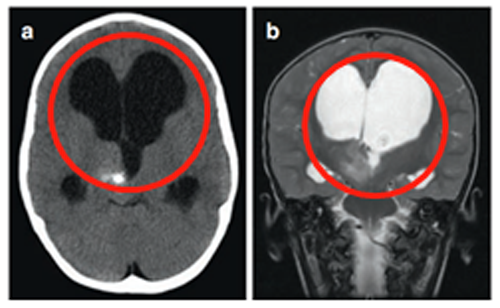

3岁患儿-丘脑病变伴钙化

3岁患儿因呕吐和巨脑畸形就医。CT及MRI显示右侧丘脑病变伴钙化及后三脑室梗阻,引起脑积水(图1)。

(图1)

在8岁、11岁和13岁时,James T.Rutka教授成功地利用第三脑室内窥镜切开术治疗脑积水(图2为系列影像),且影像显示肿瘤增大和多发肿瘤囊肿(箭头状),并逐渐出现左上肢震颤。

(图2)